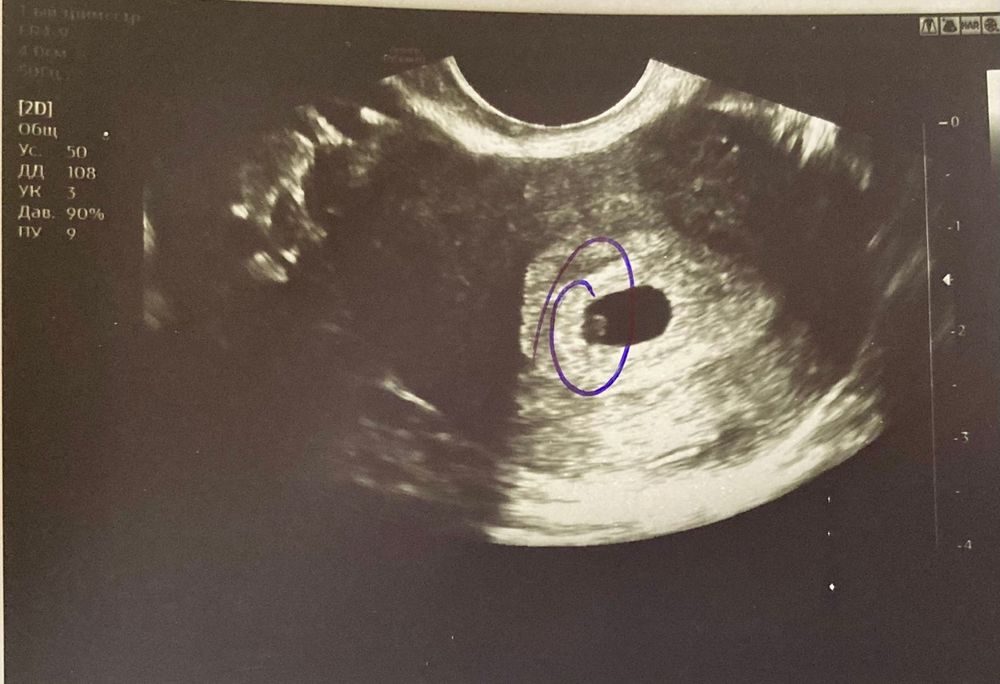

Наше первое УЗИ на 20 ДПП

Ну вот мы и дошли до этого момента 💝

Сегодня впервые встретились с моей крошкой 🤍🤍🤍

Нам подтвердили маточную беременность 5-6 недель 🤰🏻

ПЯ в матке - 7,4 мм

ЖМ - 1,8 мм

Эмбрион еще не визуализируется.

Но... рядом с ПЯ есть еще одно образование под вопросом?!

толи второе ПЯ (нам подсаживали 1), толи киста хориона - до 2,7 мм

Будем наблюдаться дальше.

Фото на память дали 📸